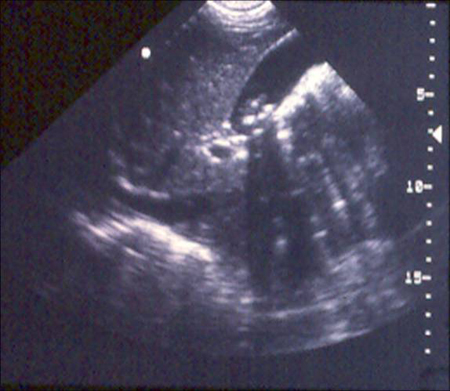

Cholelithiasis (gallstones)

Gallbladder ultrasound demonstrating cholelithiasis with characteristic shadowing

Courtesy of Kuojen Tsao; used with permission